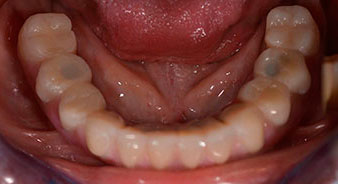

Nach der Zeit, die für die Osseointegration benötigt wird, kann die endgültige Abformung der Implantate erfolgen und entsprechend die endgültige Arbeit angefertigt werden (Abb. 19 und 20). Hier können Behandler und Patient gemeinsam entscheiden, ob diese eine Keramik- oder Kunststoffverblendung, ein Zirkon- oder Metallgerüst bekommen soll. Im vorliegenden Fall hat sich das Team um Dr. Pascu, aufgrund der unklaren Prognose der Oberkieferbezahnung und des elongierten Zahnes 24, für eine Kunststoffverblendung entschieden. Diese ist im Allgemeinen wesentlich einfacher umzustellen und der neuen Situation im Oberkiefer anzupassen.

Osseointegration

Abb. 19

Implantate

Abb. 20